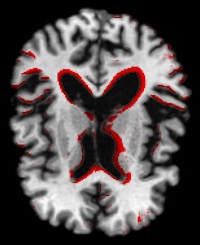

PredictAD aims to extract biomarkers from heterogeneous patient data and integrate them for objective and evidence-based diagnostics. For example its reasearch team is exploring how MRI can be used to measure atrophy in the mediotemporal lobe, which is recognized as a hallmark of Alzheimer's.

In current clinical practice, images are interpreted mostly only by visual inspection, but there is a need for objective measurements, according to Dr. Jyrki Lötjönen, the scientific coordinator of the project and principal scientist and adjunct professor of signal and image processing at the VTT Technical Research Centre in Tampere, Finland.

To meet this need, the PredictAD team has developed tools for measuring the size of the hippocampus, the atrophy rate of the hippocampus, and two approaches based on comparing patient data with previously diagnosed cases available in large databases. PET is also being studied in the project. A novel tracer developed recently especially for diagnostics of Alzheimer's disease provides promises for very early diagnosis of the disease.